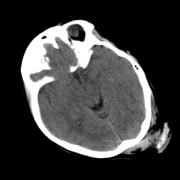

So far we have observed enhanced performance through the SA term. In this subsection, we visually illustrate how this novel term imposes smoothness between attention scores of consecutive slices, leading to more accurate predictions. Figure 2 shows plots of the attention scores assigned by SA-DMIL- and Att-MIL to the slices of three different scans (Fig. S1 in the appendix contains an analogous plot for SA-DMIL-). As expected, introducing the SA loss results in smoother attention weights. Note that the smoothness constraint of SA-DMIL effectively penalizes the appearance of isolated non-smooth attention weights that incorrectly jump over or below the threshold.

We also include visual examples of consecutive CT slices in Fig. 3. In Scan 1, the baseline Att-MIL produces a wrong prediction at scan level. When using SA, the prediction is correct since dependencies between adjacent slices have been learned. In Scan 2, both models produce correct predictions at scan level, but SA-DMIL is more accurate at slice level. This occurs thanks to the SA loss, that turns the attention scores into smoother values and, therefore, avoids random jumps up and down the decision threshold.